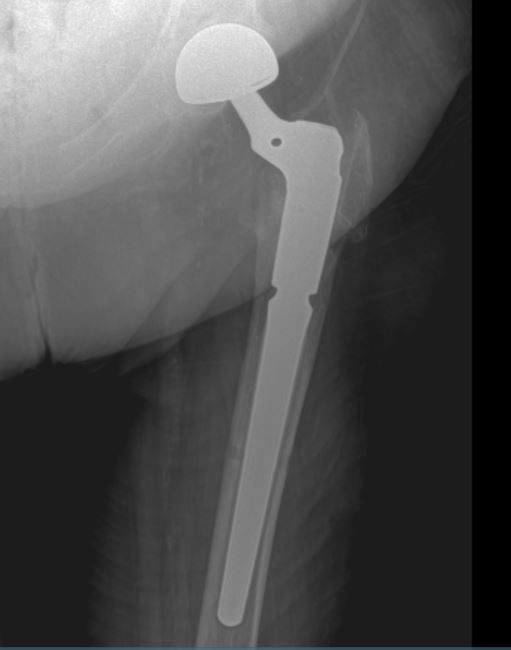

Partial Hip Replacement Xray . Total hip arthroplasty (tha), also known as total hip replacement (thr), is an orthopedic procedure that involves the surgical. In a hemiarthroplasty, also called partial hip replacement, the femoral head and neck are replaced. Modern total hip arthroplasty (tha) systems are modular. Types of hip replacement surgery: Although there are many described. In some situations, the socket part of the hip doesn't need to be replaced. This means that the femoral stem, head, acetabular shell and liner are separate pieces. Partial hip replacement/hip hemiarthroplasty is an orthopaedic procedure for the treatment of certain femoral neck fractures where the femoral head is removed and replaced. Partial hip replacement might be.

Partial Hip Replacement Xray Types of hip replacement surgery: Total hip arthroplasty (tha), also known as total hip replacement (thr), is an orthopedic procedure that involves the surgical. Modern total hip arthroplasty (tha) systems are modular. In a hemiarthroplasty, also called partial hip replacement, the femoral head and neck are replaced. Although there are many described. In some situations, the socket part of the hip doesn't need to be replaced. Partial hip replacement/hip hemiarthroplasty is an orthopaedic procedure for the treatment of certain femoral neck fractures where the femoral head is removed and replaced. This means that the femoral stem, head, acetabular shell and liner are separate pieces. Types of hip replacement surgery: Partial hip replacement might be.